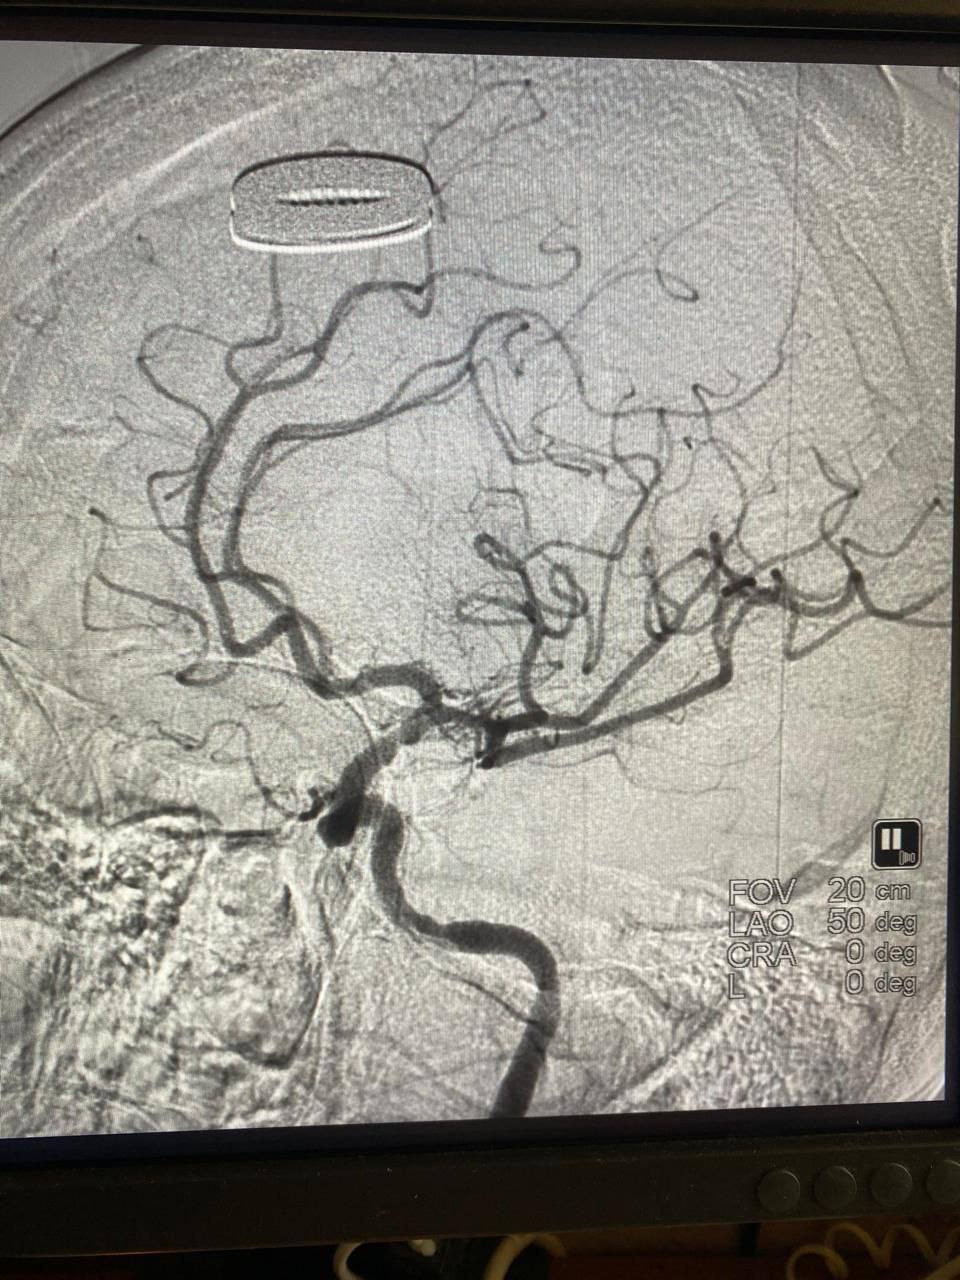

Пациентку экстренно отправили в рентген-операционную. Врачи удалили тромб и восстановили мозговой кровоток.